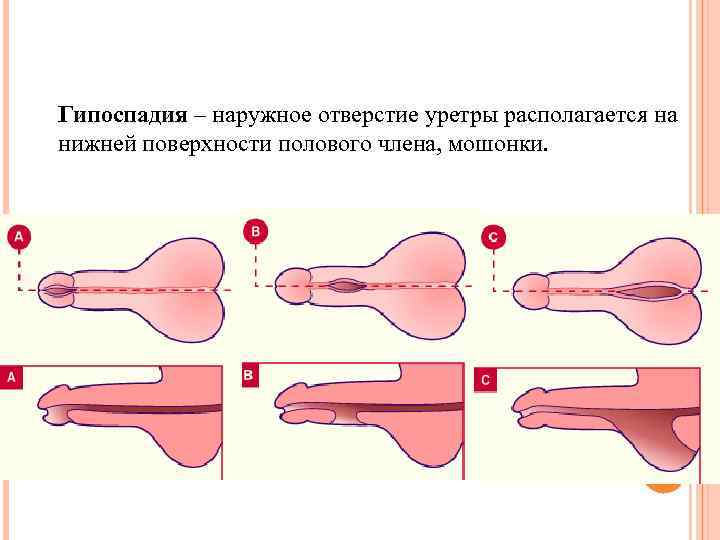

Гипоспадия – наружное отверстие уретры располагается на нижней поверхности полового члена, мошонки.

Гипоспадия – наружное отверстие уретры располагается на нижней поверхности полового члена, мошонки.

Гипоспадия – наружное отверстие уретры располагается на нижней поверхности полового члена, мошонки.

Гипоспадия – наружное отверстие уретры располагается на нижней поверхности полового члена, мошонки.